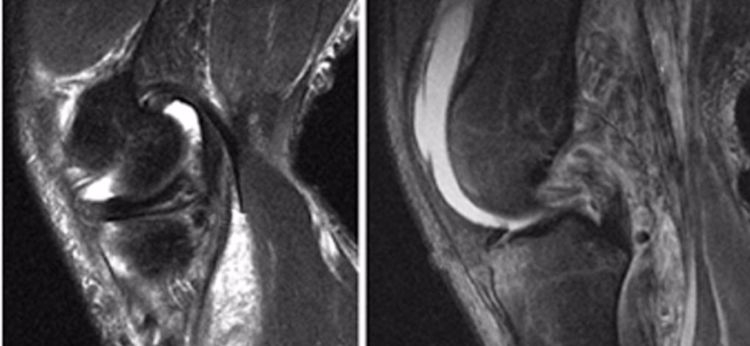

后交叉韧带撕裂的间接表现:

1.髓内水肿:主要是胫骨上段前方的骨水肿,就是平常所说的挡板征或仪表盘征。

如果站立位被撞击膝关节后上方则表现为股骨后髁水肿,不常见。

2.撕脱骨折:后交叉韧带胫骨附着点的撕脱骨折较常见。表现为胫骨平台后部有线形的T1加权低信号,T2加权,STIR高信号的骨折线,撕脱的碎片和后交叉韧带相连而韧带的连续性未见中断。